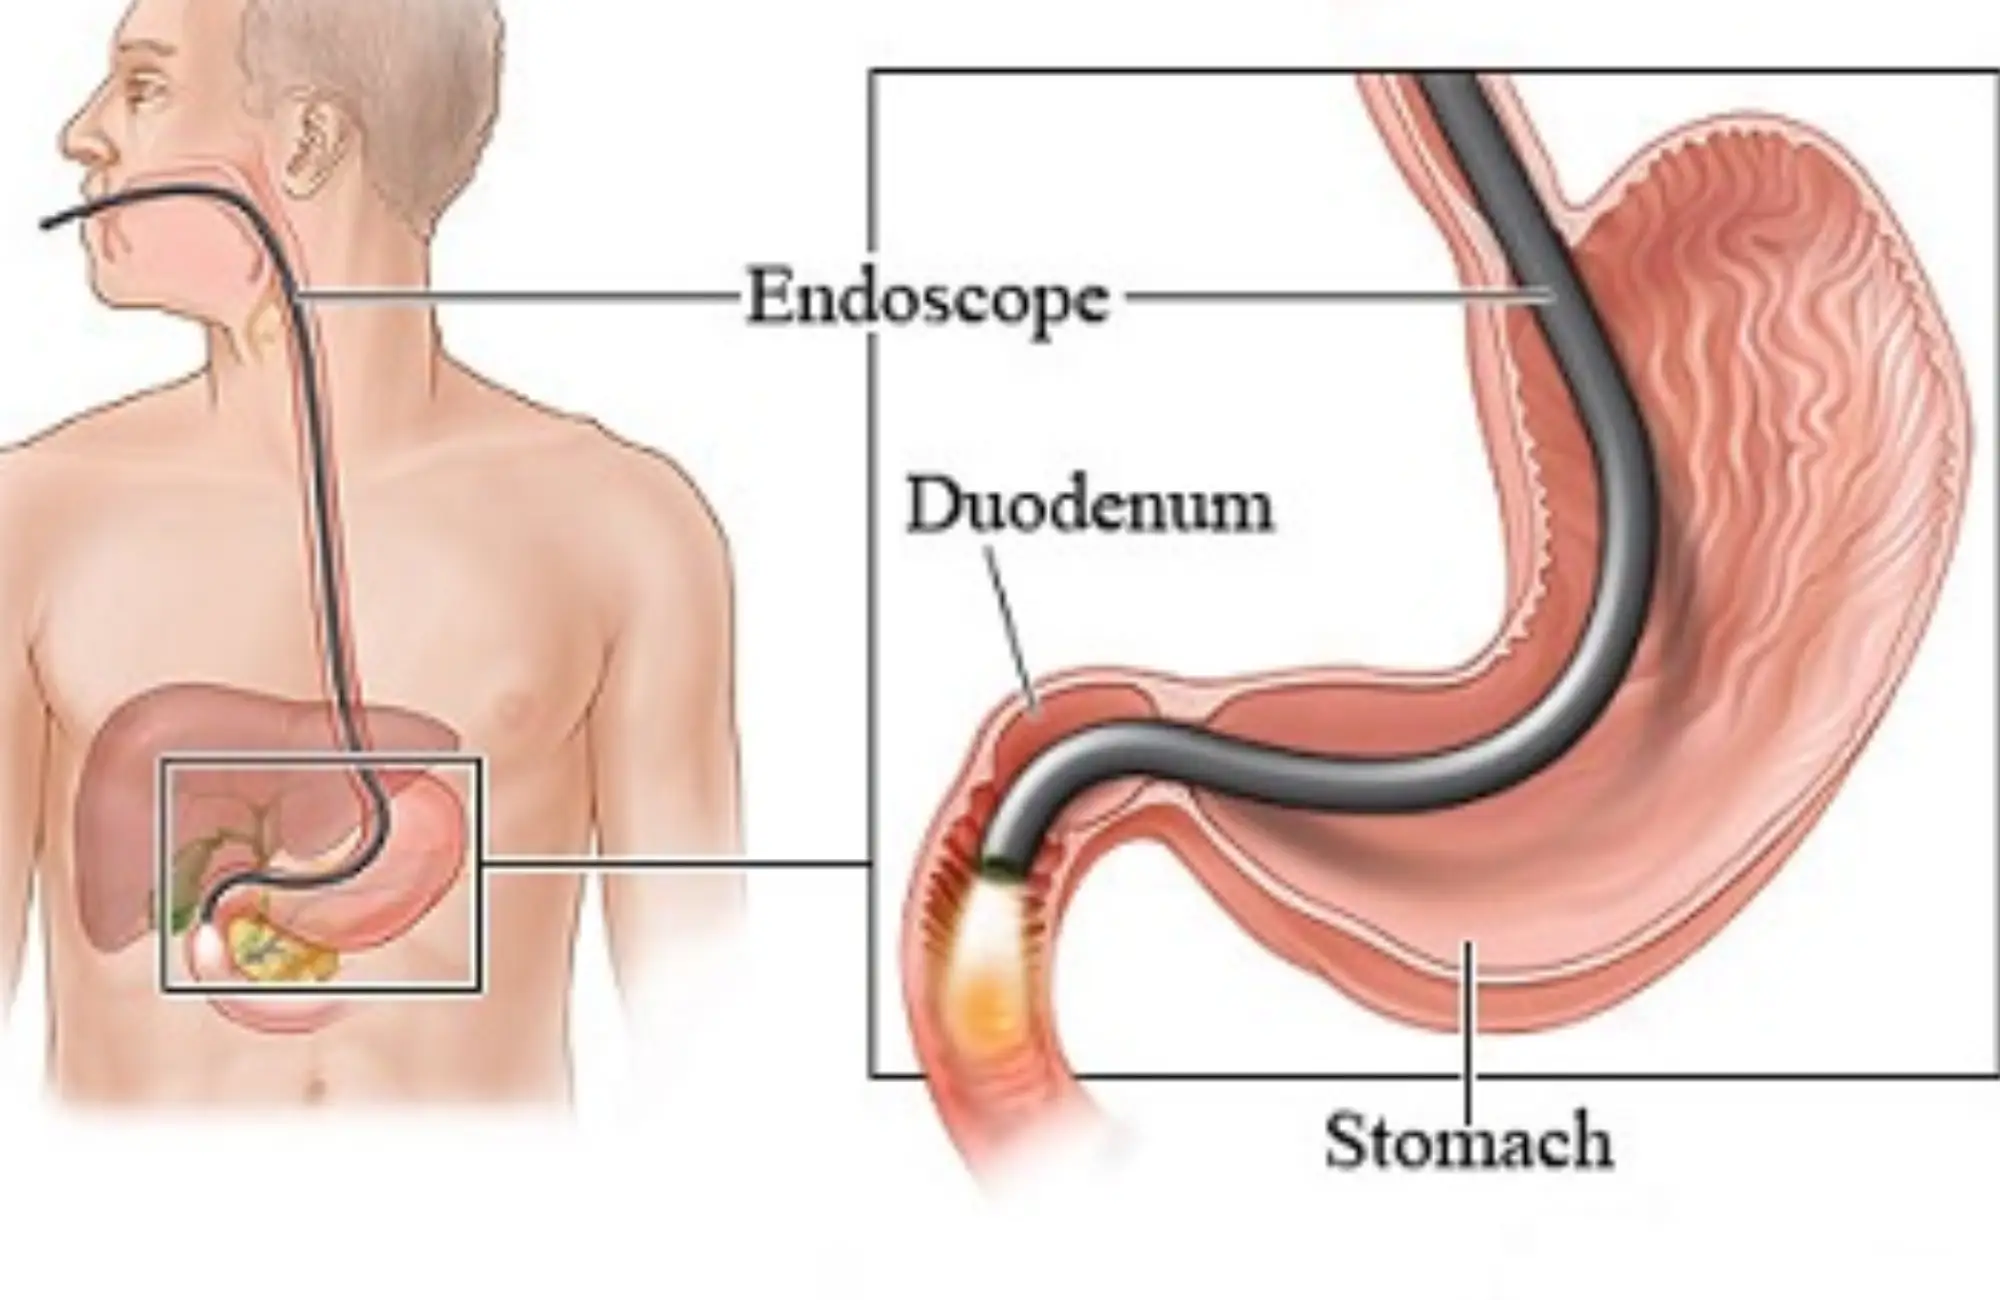

Endoscopy cost in Ahmedabad

If you are someone who is interested in finding about the Endoscopy...